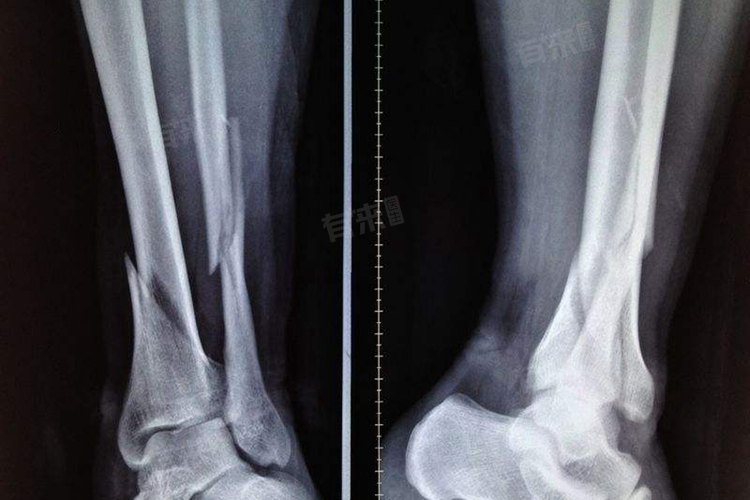

骨折线欠清是主要描述的是骨折线在X光片、CT或磁共振成像等影像学检查中的清晰度不足。其可因营养不良、护理不当、对线不佳、愈合过程及疾病因素所致,常伴骨折相关症状。诊断依赖影像学检查,治疗则根据病情轻重选择保守或手术方法。

- 骨折线欠清的诊断主要依赖于影像学检查,包括X光片、CT和磁共振成像等。医生会根据这些影像资料来判断骨折线的清晰度、骨折的类型、程度和愈合情况。在诊断过程中,医生还会考虑患者的病史、症状和体征等信息。